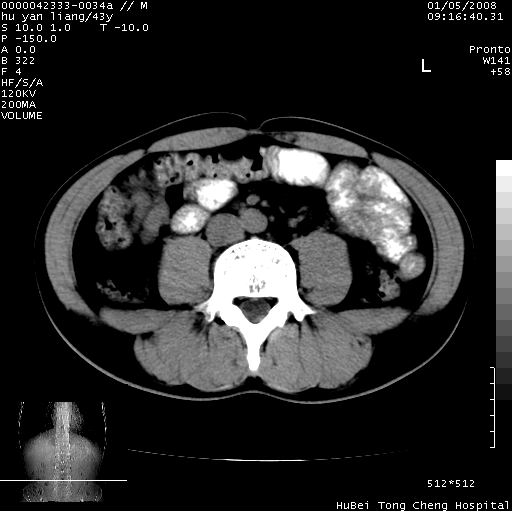

患者 男,43岁。右上腹不适1年余。既往有“肝右叶肝脓肿”病史,经保守治疗后痊愈。

b超提示:1)肝右叶肝内胆管结石。2)肝右叶占位性病变待排。

上中腹部ct轴位平扫+增强扫描(层厚10mm,螺距1.0,重建间隔10mm),图像如下:

肝右上叶偏后方较大团片状钙化灶,支持:肝脓肿后遗改变!

肝右叶后段团块状钙化灶,结合病史考虑肝脓肿痊愈后表现。